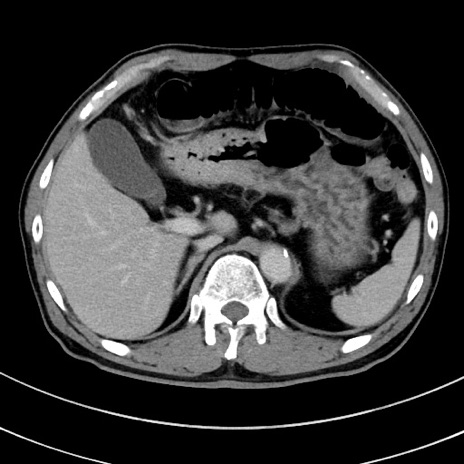

冠状断像

【症例】 60歳代男性

【主訴】 黒色吐物

【現病歴】 4日前から嘔気自覚、2日前の朝食後にも嘔気あり、自分で手で嘔吐反射起こし嘔吐したところ血が混ざっていたため受診。

【既往歴】 5年前汎発性腹膜炎を伴う急性虫垂炎で手術、高血圧、前立腺肥大症、高脂血症

【身体所見】 腹部正中に手術癩痕あり 腹部平坦・軟圧痛なし膨満感あり

【データ】WBC 8400、CRP 4.54